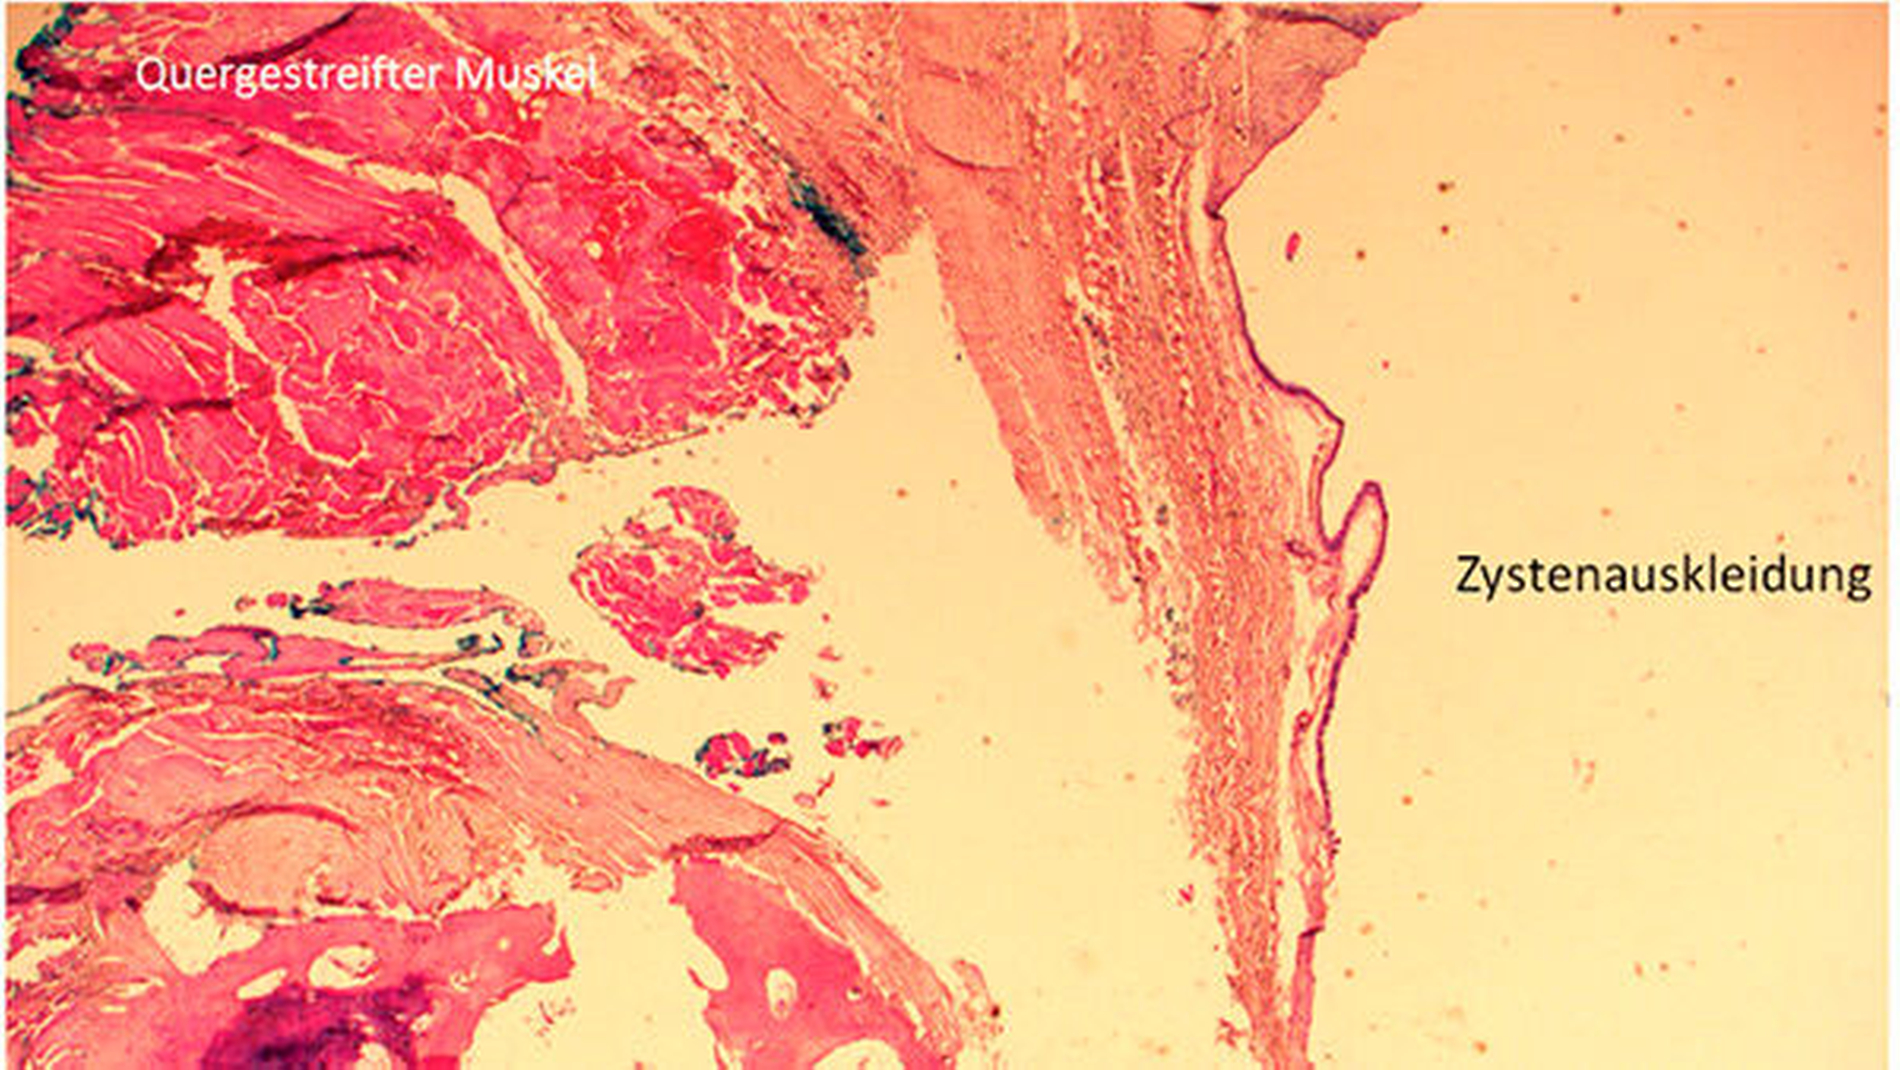

Durch die Befunde der anamnestischen, klinischen und MRT-Untersuchungen konnte die Diagnose einer medianen Halszyste gesichert werden. Die operative Entfernung der zervikalen Raumforderung wurde anschließend mit dem Patienten vereinbart und dann in Allgemeinnarkose über einen extraoralen Zugang durchgeführt (Abbildung 3a). Bei der intraoperativen Enukleation des zystisch imponierenden Gewebes konnte die Verbindung zum Os hyoideum eindeutig dargestellt werden (Abbildung 3b). Das raumfordernde Gewebe wurde dann mit dem gesamten medianen Anteil des Zungenbeins durch kontinuitätsunterbrechende Resektion entfernt (Abbildung 3c). Die feingewebliche Begutachtung des entnommenen Gewebes bestätigte in den histopathologischen Präparaten die klinisch und radiologisch gesicherte Diagnose einer medianen Halszyste (Abbildung 4).